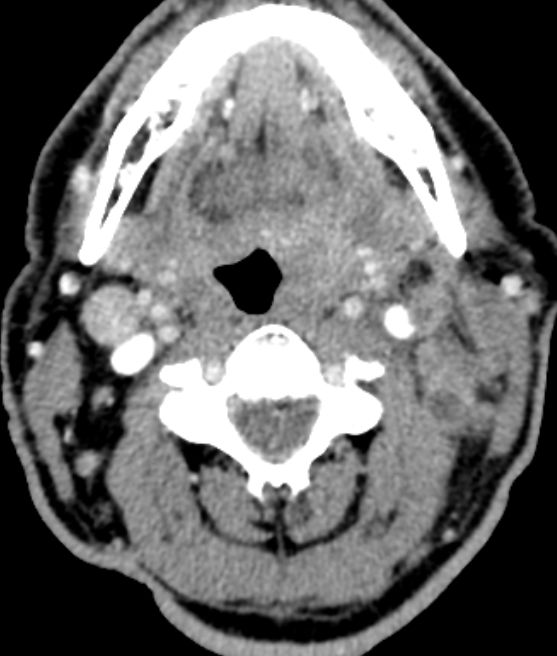

64-jähriger Mann mit tumoröser Raumforderung der linken Tonsille. Die primäre Histologie war verdächtig auf ein entdifferenziertes p16-positives Plattenepithelkarzinom. Bei der Radikaloperation wurden 84 Lymphknoten der Level 2-4 beiderseits entfernt, von denen 55 metastatisch befallenen waren. Zusätzlich wurde ein nicht zugänglicher Lymphknoten unterhalb der Karina festgestellt. Die transösophageale Punktion dieses Lymphknotens ergab den Verdacht eines malignen Lymphoms. Daraufhin wurden von den zervikalen Lymphnoten zusätzliche immunhistochemische Untersuchungen durchgeführt. Nach Vorliegen der Referenzpathologie handelt es sich um den seltenen Fall eines sarkomatoiden Lymphom oder eines histiozytischen Sarkoms. Diese Zellen sehen einem entdifferenzierten Plattenepithelkarzinom sehr ähnlich. | ||

Zahlreiche vergrößerte zervikale Lymphknoten.![]() |